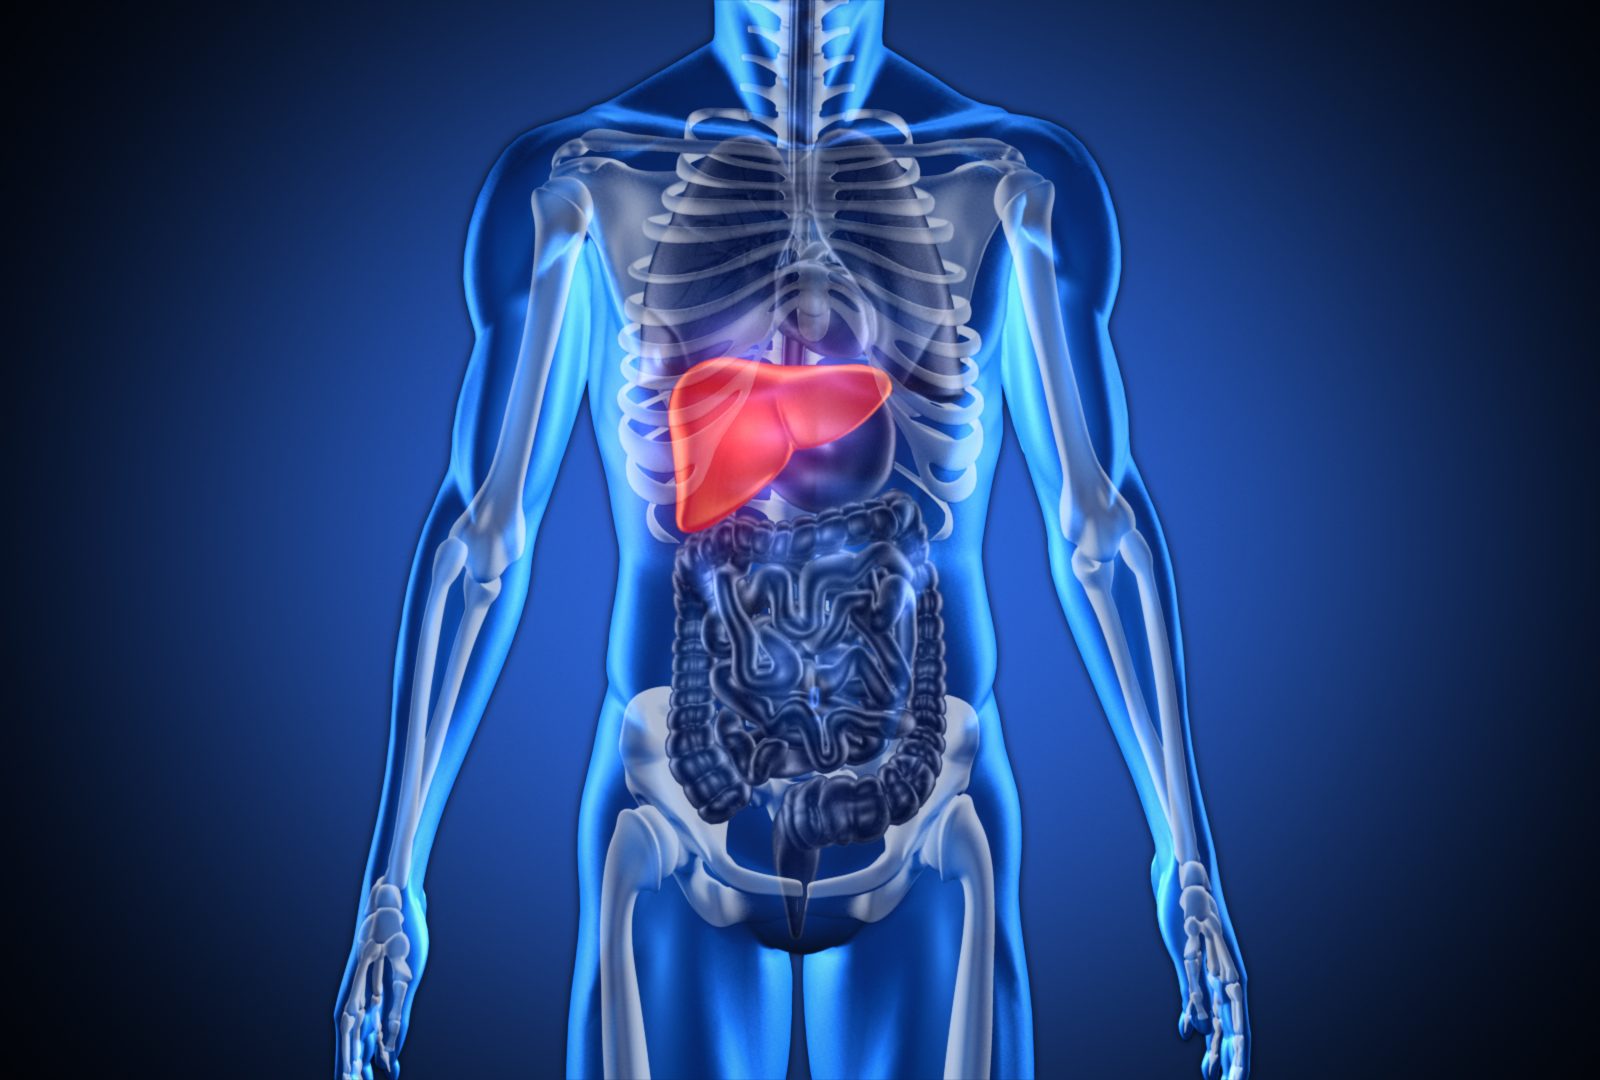

Изображения и визуализация внутренних органов человека

Раздел: Секреты мастерства